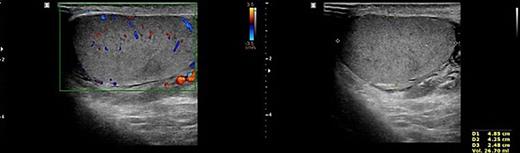

To prevent the patient from further self-injury, simple therapeutic restraint of both arms was performed with the patient’s consent, and sedative medication was administered. He was closely observed in the intensive care unit to monitor his hemoglobin and systemic conditions. Additional transfusion treatment was provided as needed. Psychiatric medicines including antipsychotics and sedatives (Clozapine 125–250 mg/day, haloperidol 2.5–5 mg, and lorazepam 1–2 mg/day) were prescribed by a psychiatrist. After 5 days of taking the psychiatric medication, the patient no longer reported the impulse to harm himself, and was able to release the simple restraint on both arms. No further self-harm occurred until he was discharged, presumably due to the proper effects of taking psychiatric medication. Anticoagulant agents (5 mg apixaban, twice per day), subcutaneous heparin injection (5,000 IU, twice per day), and alprostadil (10 mg, once per day) were given for circulation to prevent the thrombosis of vessels. On POD2 from the first operation, a testicular scan with technetium pertechnetate revealed the viability of the remnant left testis compared with the amputated right testis (Fig. 7). On POD4, contrast-enhanced CT showed the enhancement of the vessel into the testis (Fig. 8). On POD7, scrotum Doppler ultrasonography revealed the Doppler signal in the parenchyma of the testis (Fig. 9). Testosterone levels increased after the surgeries and normalized on POD5 (Fig. 10). He was discharged on POD9 without any skin complication (Fig. 6c). After discharge, he returned to our clinic for follow-up on POD13 and 23. On the visit, laboratory follow-up including testosterone and free testosterone was checked and confirmed as normal (Fig. 10).

We performed five examinations to check the viability of the replanted testis. First, in the operating room, we used indocyanine green after replantation (Fig. 4). Indocyanine green fluorescence perfusion showed testicular perfusion, which enabled the immediate checking of the viability of vessels. This procedure is appropriate for checking the viability of microscopic vessels that may be damaged during a milking test. Second, a testicular scan showed the viability of the testis (Fig. 7). One testis is markedly different from the lesion of orchiectomy. However, the scan resolution was low because of a wide range of arterial courses and the disturbance of the urethral catheter or bladder. Third, contrast-enhanced CT displayed the vascularity of the testis and the surrounding parts (Fig. 8). However, the shooting time to the enhanced phase could affect the failure of the vascularity of the testis. No protocol for this case has been established in our institute; therefore, CT was a nonspecific tool for testicular examination. Fourth, ultrasonography efficiently showed the vascularity inside the testis (Fig. 9). However, skin wound could inhibit or limit ultrasonography. Fifth, we indirectly checked the testicular function based on testosterone levels (Fig. 10). A laboratory examination should be performed continuously. However, this procedure could be limited among hypogonadal men, and the separate testicular function of each testis could not be easily identified. Nevertheless, these techniques will help determine the viability of the testis in specific situations.